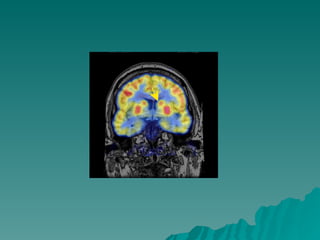

GLOBO PÁLIDO CORONAL